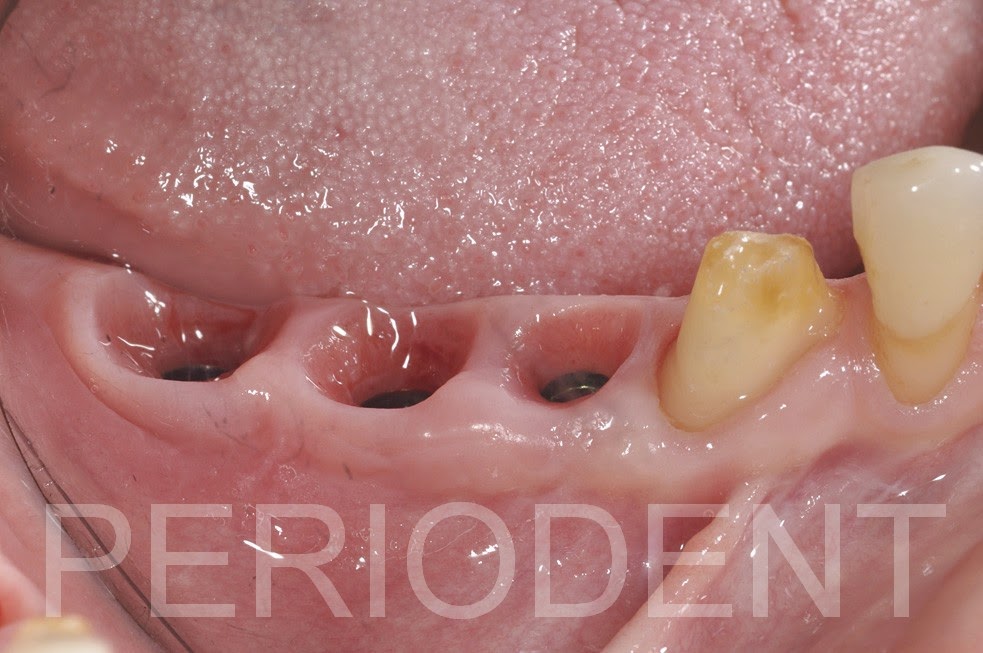

癒合後

取模裝上正式假牙